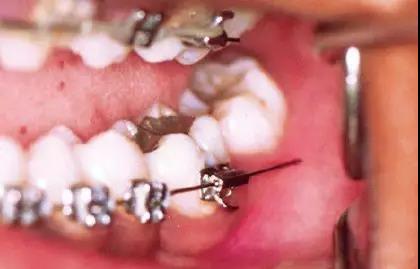

2.固定矫治器

微信图片_20200210130929

疫情期间注意事项:

(1)挂牵引橡皮筋的患者,每次取戴橡皮筋时做好手卫生(勤洗手)。

(2)做好口腔清洁,保持牙齿与矫治器的清洁卫生。

(3)进食时注意避免啃咬坚硬事物,减少矫治器损坏与脱落。

(4)因为疫情短期无法复诊:与主治医生取得联系,必要时拍摄口内照片图文咨询。

紧急情况处理方法:

(1)钢丝滑出:将弓丝向滑出相反方向轻微移动将其复位。若无法复位,则使用粘膜保护蜡或口香糖包裹末端防止扎嘴。

微信图片_20200210130932

(2)钢丝扎嘴(结扎丝与弓丝):若为结扎丝扎嘴,可以采用圆钝物体比如铅笔头将结扎丝重新压到弓丝的下方。若为主弓丝扎嘴,则建议使用粘膜保护蜡或口香糖包裹扎嘴部位。